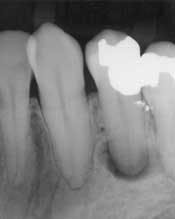

At first glance, the most obvious difference between the traditional patient exam and the digital new-patient exam is in the size of the radiographs. It is now possible to take a bitewing, a periapical film, or a panorex and show it on a large computer monitor that is visible to both the dentist and the patient (Fig. 1). With a laser pointer, it is possible to demonstrate normal or pathologic bone level, periapical pathology, tartar on teeth, the pulp chambers, and dental caries. Frequently, after just a few explanations, patients are able to detect other cavities, calculus, or areas of bone loss. When this happens, the level of ownership and responsibility taken by the patient increases significantly.